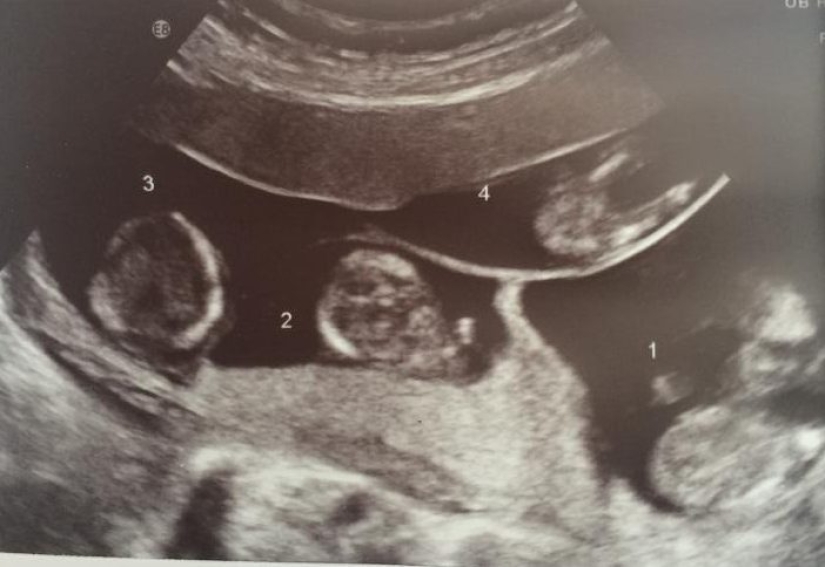

The woman could not get pregnant for a long time due to health problems, but in 2014 the test showed a long-awaited positive result. What was the surprise of the newly minted parents and doctors when it was discovered that they were expecting not one child, but four at once!

Quadruplets conceived without artificial insemination are born once per 700,000. In the UK, this case is unique. Katelina conceived four fraternal twins at the same time, which are not similar to each other. Now the children have already turned 4 years old.

The very first experiences were associated with the normal course of such a complex pregnancy. Doctors initially advised the woman to leave only two fetuses, because there was a risk of losing them all and a threat to the health of the mother herself. But, Katelina decided to leave everything as it is.

Katelina was admitted to the hospital for preservation in January 2015, at 27 weeks of pregnancy. The quadruplets were born by Caesarean section in February, at the 30th week of pregnancy.